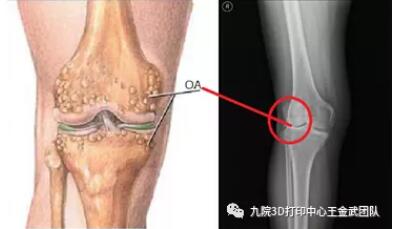

膝关节骨性关节炎是OA的最常见类型,是一种慢性、无菌性、进行性侵犯关节的炎症,最终致关节疼痛,畸形和功能障碍,影响病人的活动能力和生活质量。资料表明60岁以上人群,几乎100% 有膝关节退变的组织学表现,60%~80%可见OA的X线征象,其中20%有疼痛和活动受限;国内的发病率高达8.3%。

下肢力线的测量一般采用负重位下肢力线全长X线片进行测量。

除此之外,胫股角也常被用作膝骨关节炎的诊断。胫股角是股骨长轴和胫骨长轴相交于膝关节中心而形成的向外侧的夹角,平均为174°图片图片。